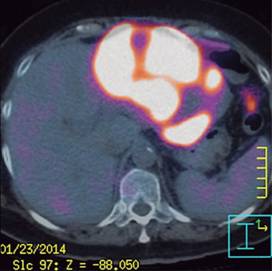

Se solicitaron marcadores tumorales, antígeno carcinoembrionario (ACE), alfa-fetoproteína (AFP), CA 125 y CA 19-9, los cuales fueron reportados dentro de rangos normales, por lo que se decidió realizar un PET/CT, el cual confirmó múltiples lesiones en lóbulo hepático izquierdo de 13.6 x 11.5 x 9.6 cm que confluyen y son hipermetabólicas, asociadas a adenopatías mediastinales también hipermetabólicas compatibles con enfermedad metastásica de primario desconocido (Figuras 1, 2 y 3).